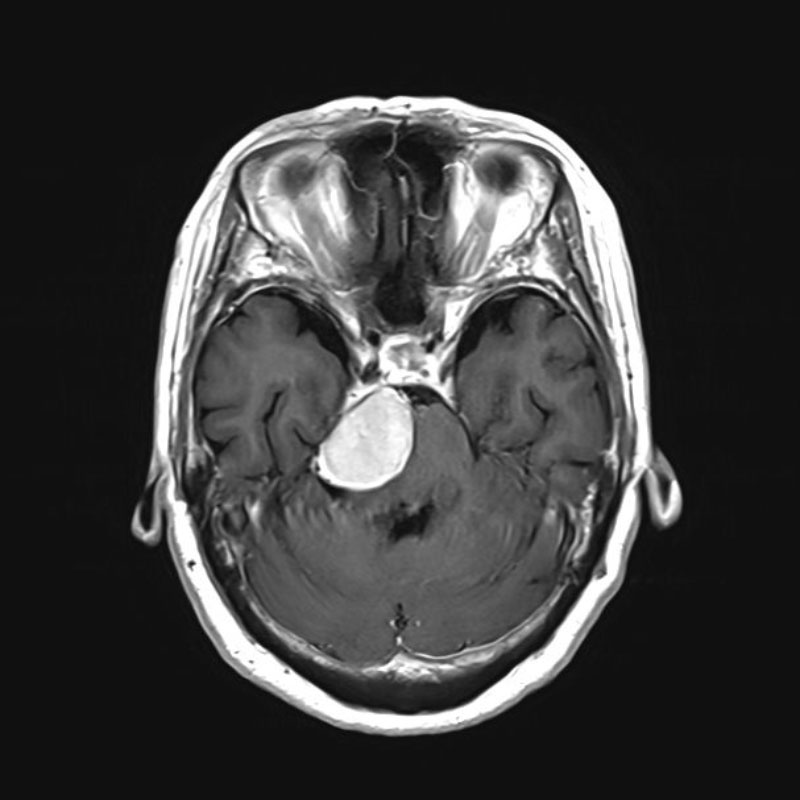

No.’25_26 手術前1

No.’25_26 手術前2